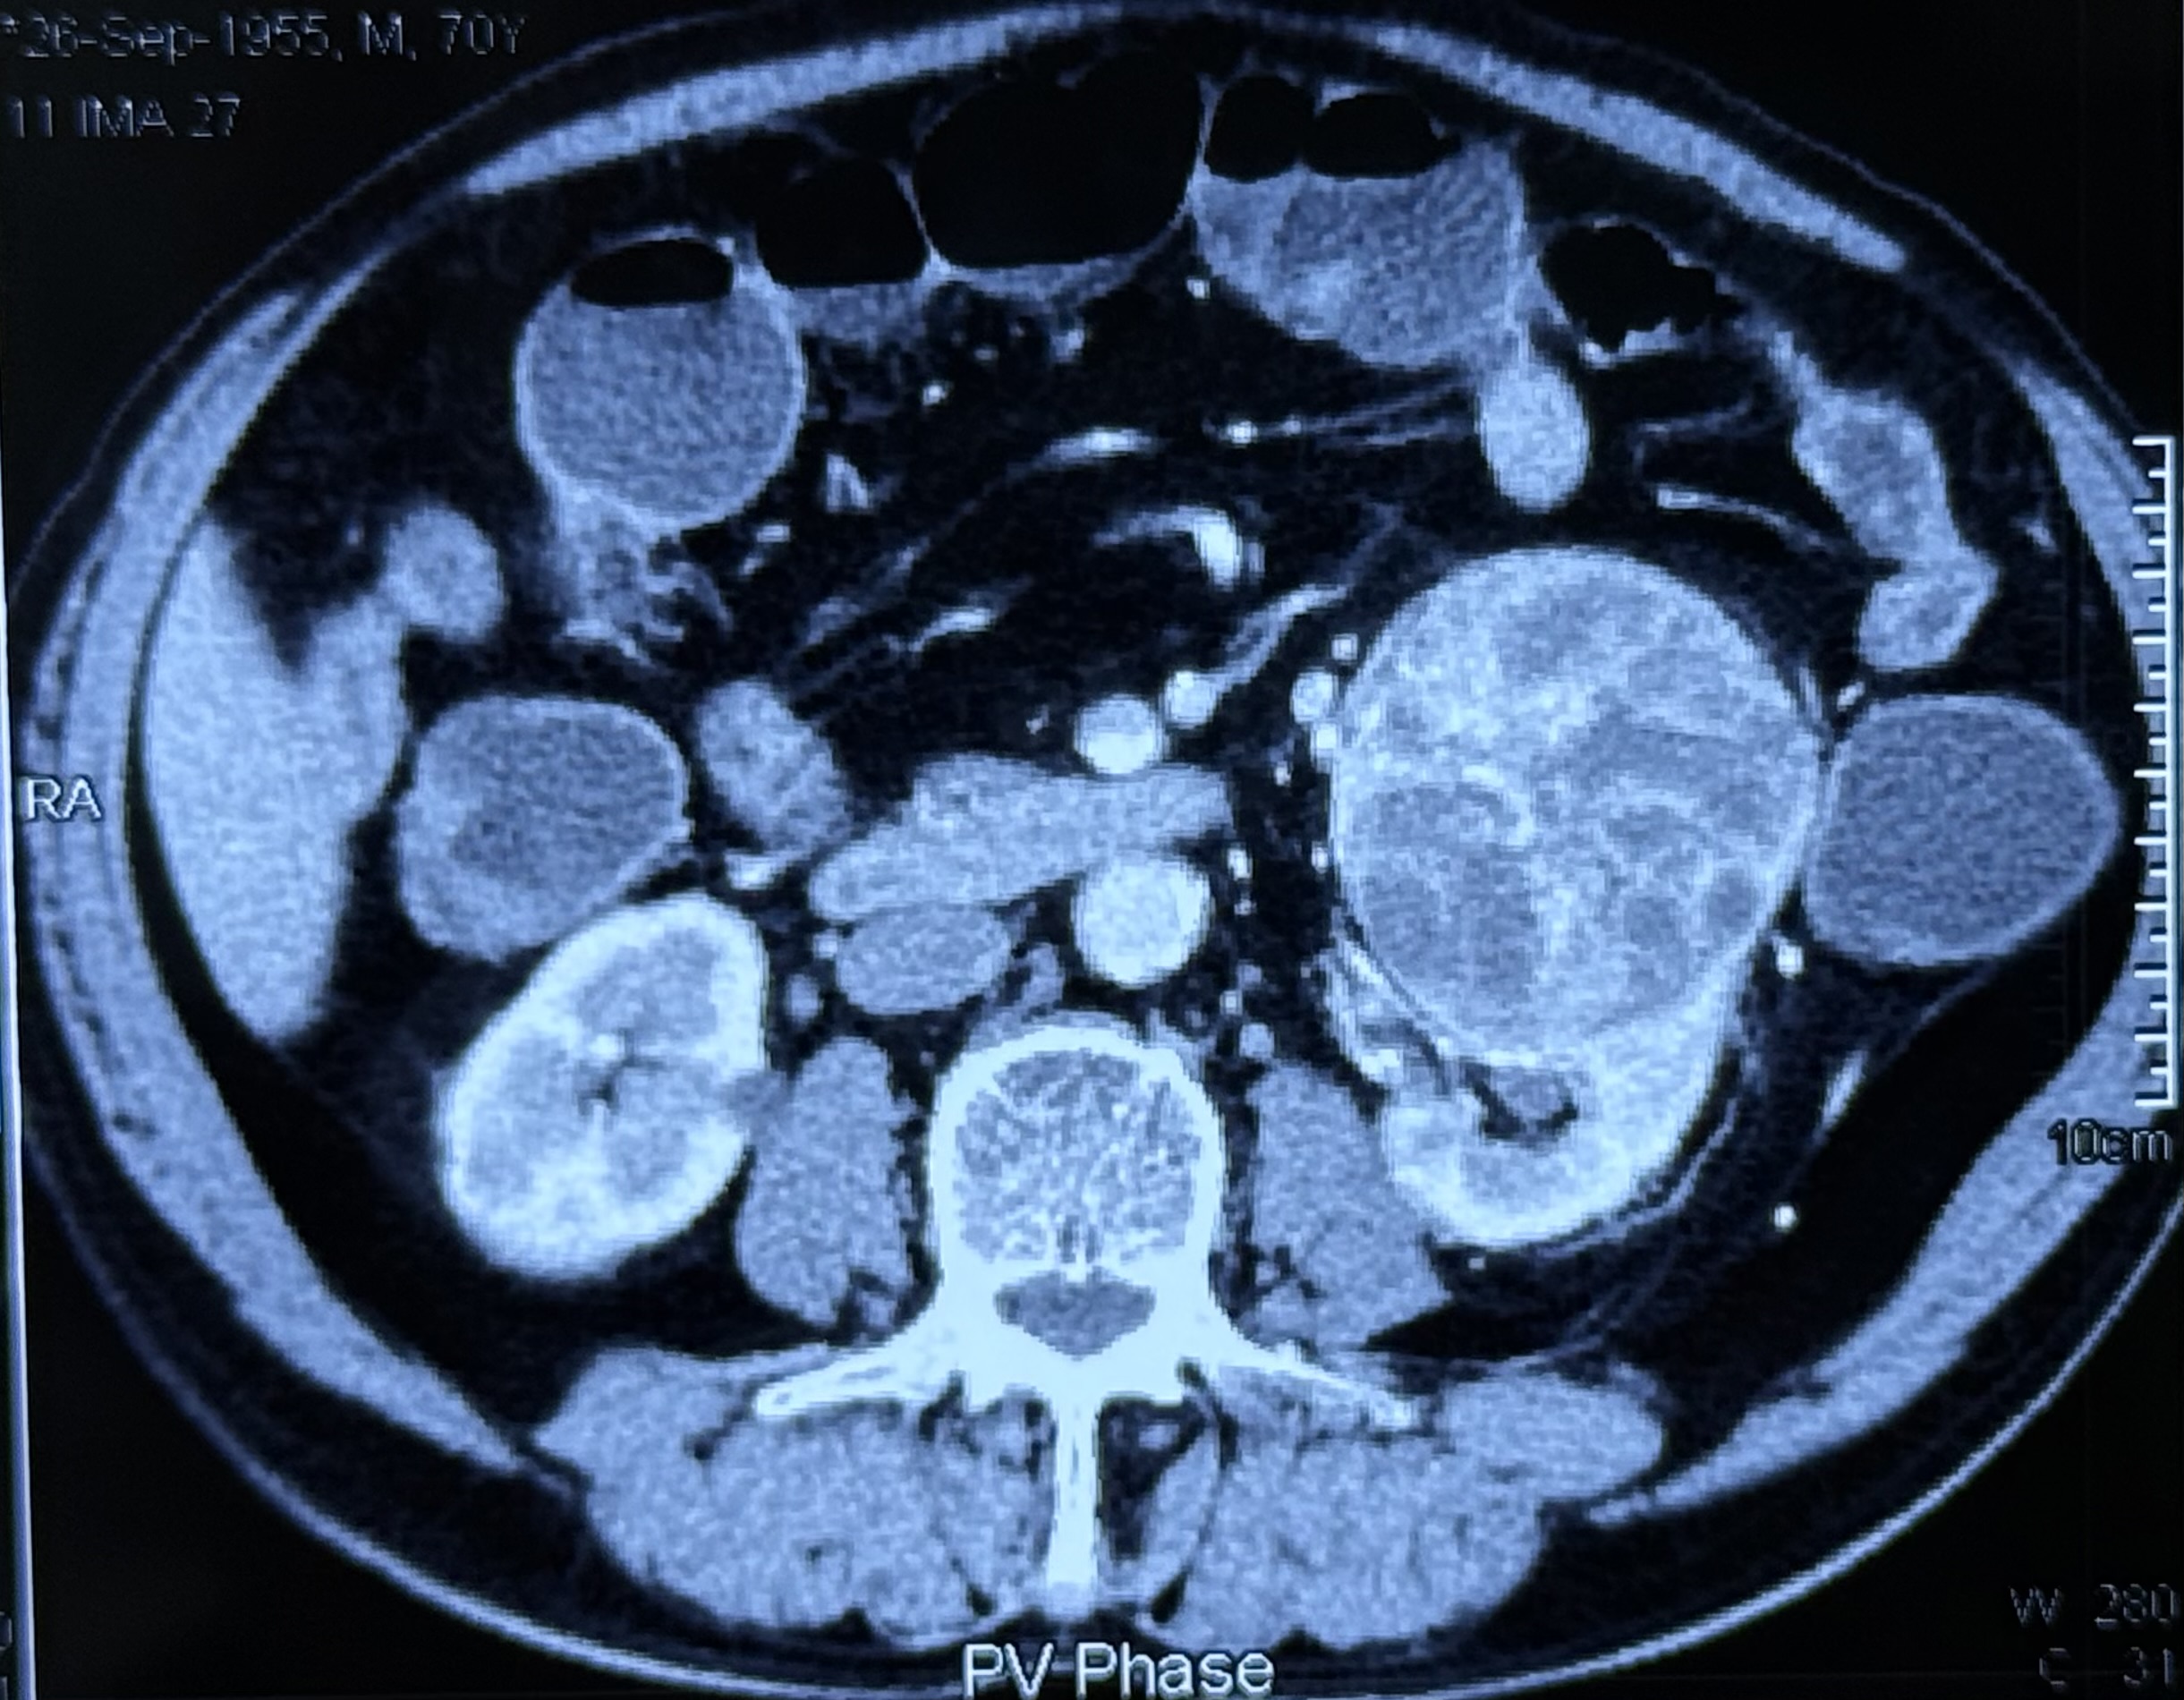

mRCC

mRCC treated with IO-TKI

Excellent prognosis even in case of metastatic renal clear cell carcinoma Both the study with Pembro + Axi (KEYNOTE-426) & Nivo + Cabo (CheckMate-9ER) showed Comparable OS/ORR; Nivo+Cabo with slightly stronger PFS, Pembro+Axi with longest OS follow-up.